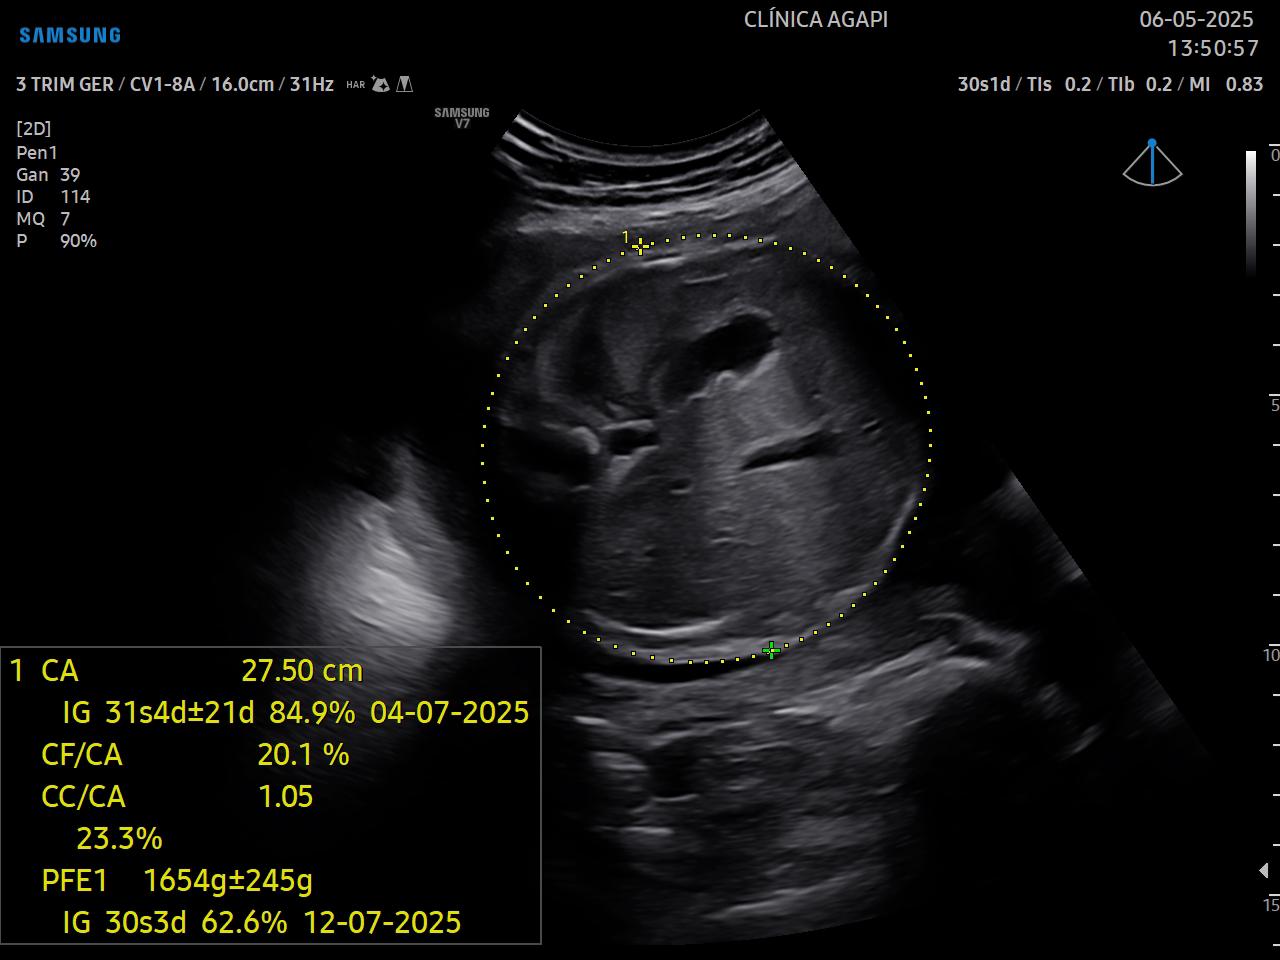

Exame realizado geralmente no 3º trimestre, avalia o crescimento e bem-estar fetal.

O doppler materno inclui a avaliação das artérias uterinas e o doppler fetal: artéria umbilical, artéria cerebral média, relação cérebro-placentária e quando necessário, ducto venoso.